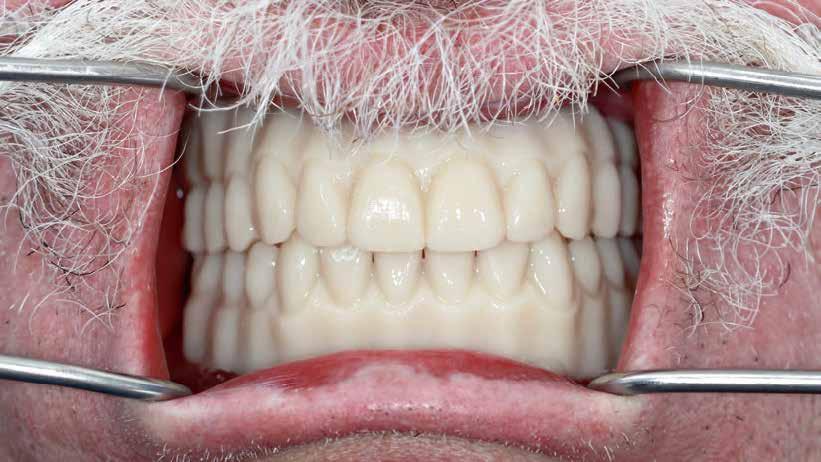

KIRÁLYKATEGÓRIA –FRONTFOG-MEGOLDÁS

Implantátum-protetikai ellátás digitális tervezéssel

Egyetlen frontfog pótlása most is – akárcsak korábban – a királykategóriába tartozik. Bármely kis formai vagy színhiba kíméletlenül megmutatkozik minden mosolynál. Ezzel hihetetlen szintet nő, vagy csökken a páciens életminősége. Stefanie Flentje esetbemutatása ismerteti, hogyan valósíthatunk meg sikerrel implantátum elhorgonyzású borítókoronát a frontterületen.

A 64 éves hölgypáciens esztétikus pótlást kívánt 21-es foga helyén, amelyet balesetet követően 2022-ben távolítottak el. Az összes foga egészséges és vitális volt, így a 21-es régióba implantátum került, amelyre cirkónium-dioxid koronát terveztünk. Az implantátum típusát, pozícióját, átmérőjét egyedi anatómiai adottságainak és az adott helyviszonyoknak megfelelően választottuk meg.

Előkezelés

2023 elején került behelyezésre a 21-es régióba egy Camlog Tissue Level implantátum, 4,3 mm átmérővel és 13 mm hosszal. Az eseménymentes gyógyulást követően az implantátum csontosodását a Periotest-eljárással ellenőriztük, majd hagyományos zárt kanalas lenyomatvétel után ideiglenes ellátás készült (2–4. képek).

Próba és behelyezés

A felépítmény próbája és behelyezése a szájba a segédelemmel történik. Az emergenciaprofil kezdetben még

enyhén anémiás (vérszegény – a ford.), de gyorsan újra telítődik, tökéletesen illeszkedve a szituációhoz (36–42. képek)

A páciens a DD cube One koronát választotta, ami szín és transzparencia szempontjából is nagyon harmonikusan illeszkedett a teljes képhez (43–44. képek)